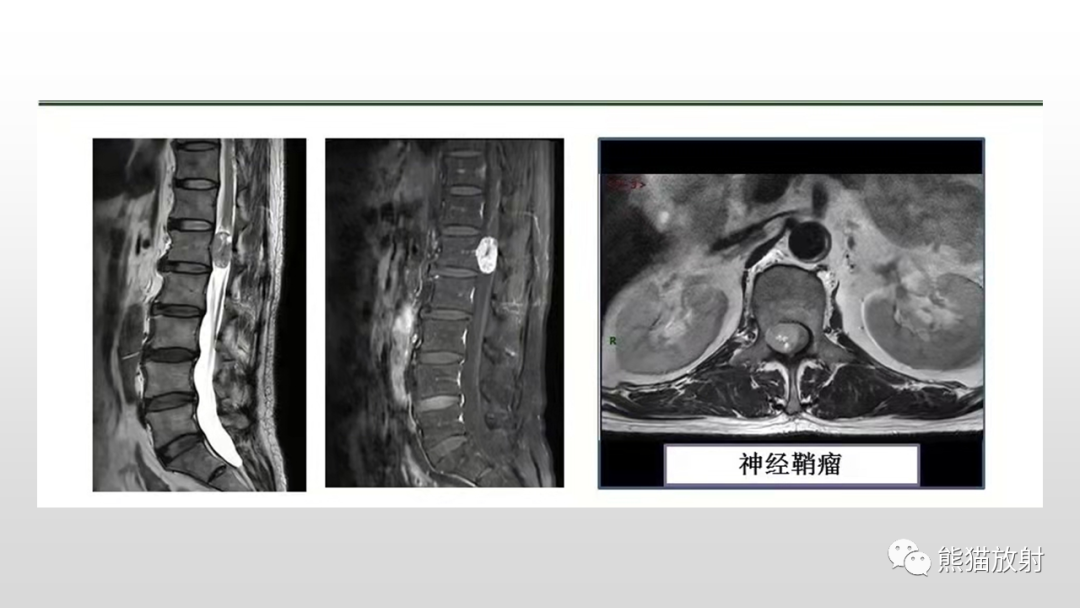

三叉神经鞘瘤1例MR影像表现